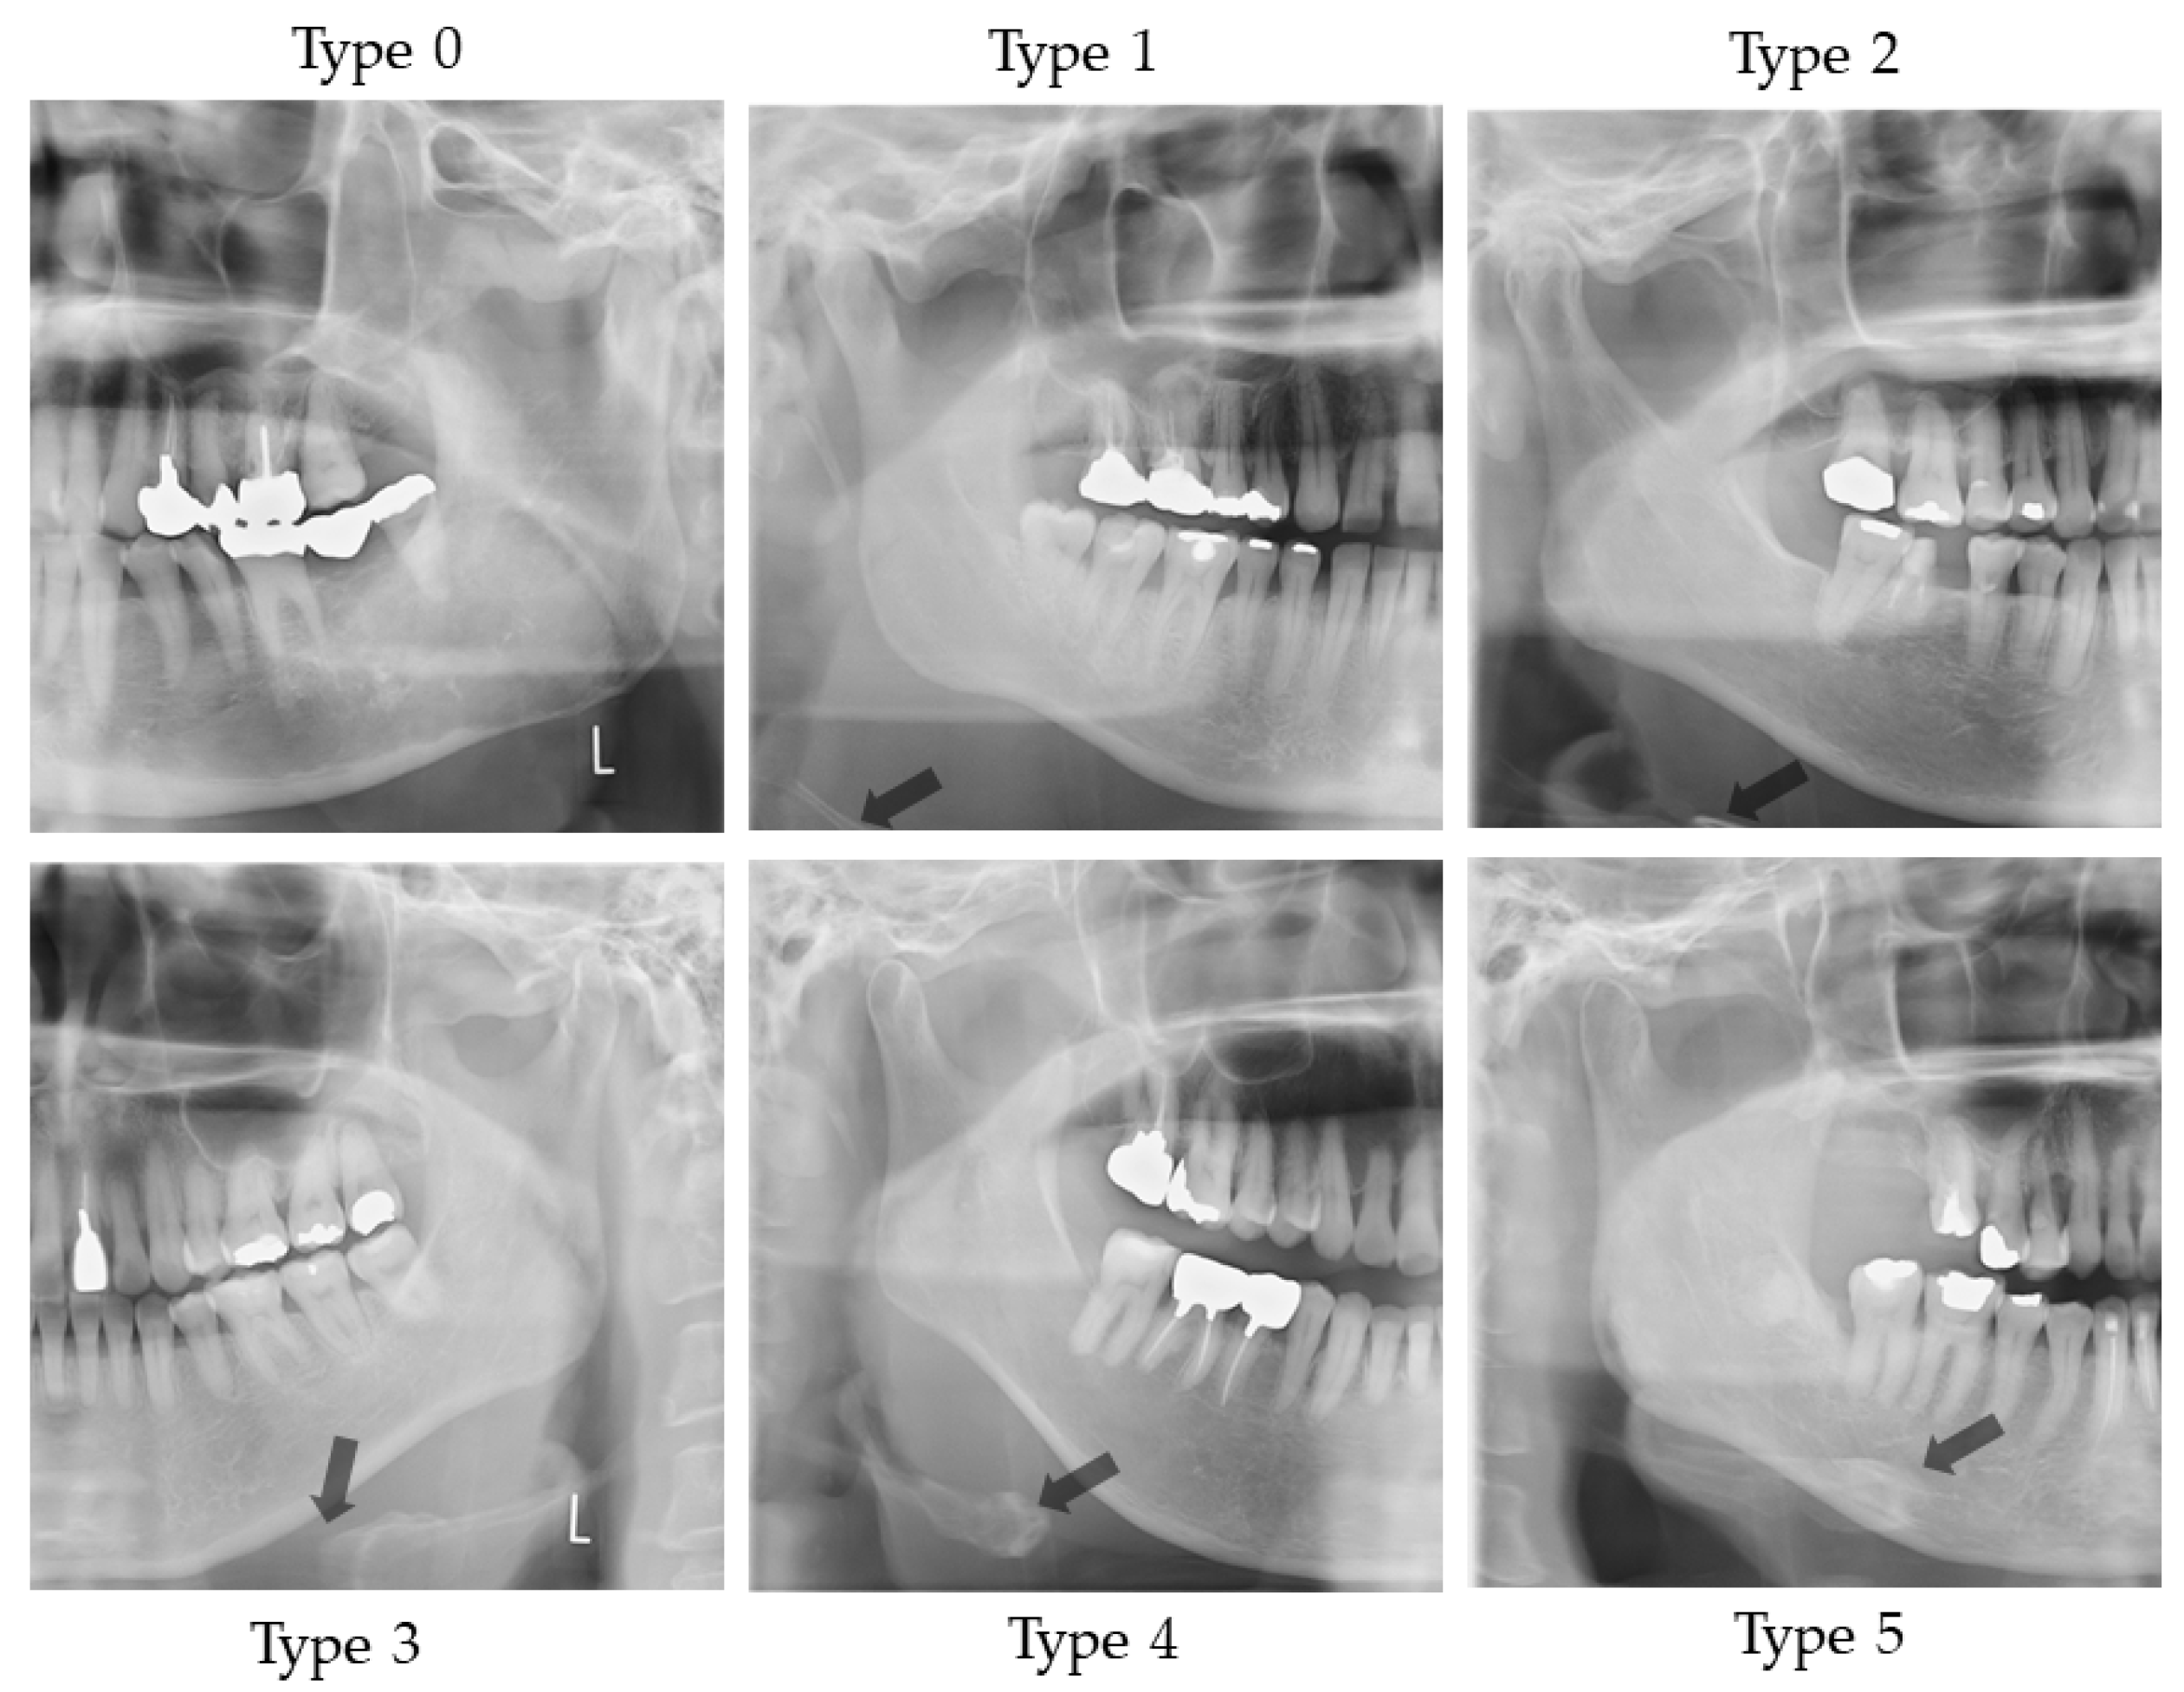

2.4.1. Vertical Hyoid Bone Position

| Vertical Hyoid Bone Position | Dysphagia (+) | Dysphagia (−) |

|---|---|---|

| Type 0 | 20 | 2 |

| Type 1 | 10 | 8 |

| Type 2 | 4 | 5 |

| Type 3 | 7 | 10 |

| Type 4 | 3 | 1 |

| Type 5 | 3 | 4 |